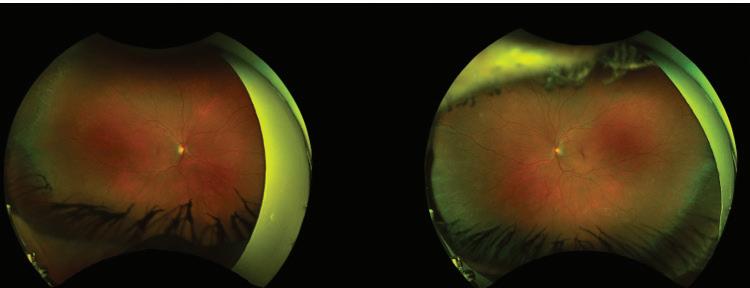

From a campus culture standpoint, the lowest preintervention question scored was verbal or physical abuse by other students, faculty, and personnel.

Table 1. Medical Student Stressor Questionnaire Results

While slight increases occurred post-intervention, they were still all below 1. Increases may have been due to poorly perceived interactions during rotations and/or variability amongst participants completing the surveys. Overall, these low scores indicate that the campus emphasized student safety during this year. The Guthrie campus offers student support from campus-specific faculty as well as from overarching school faculty in case of any abusive behavior.

The authors feel the events provided, while not showing statistical significance, still had an individuallevel impact. By organizing the events, students were provided a carved-out time where they could actively focus on wellness, connecting with other students and the local community. Wellness is a dynamic process, that can change both short term and long term. As such, wellness may have increased during the events themselves, and fluctuated afterwards depending on social, emotional, and academic influences. The lack of statistical significance could be attributed to the low sample size. Prior work has shown that other interventions, such as yoga, also had a positive effect on student wellness, further supporting the implementation of wellness activities (20).